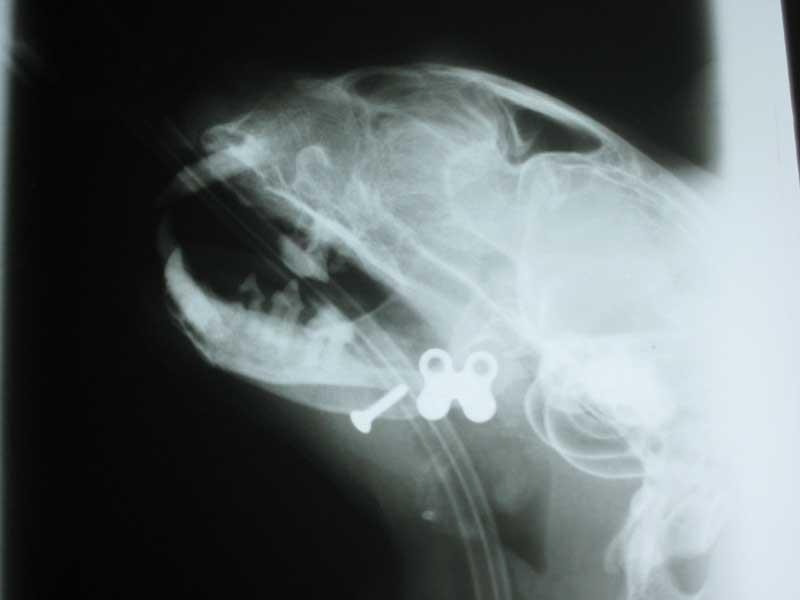

Dental Procedures

Dental procedures can be carried out at either of our surgeries using advanced dental instrument and and high speed hand tools. This allows dental procedures to be carried out effectively, quickly with minimal trauma to the mouth.